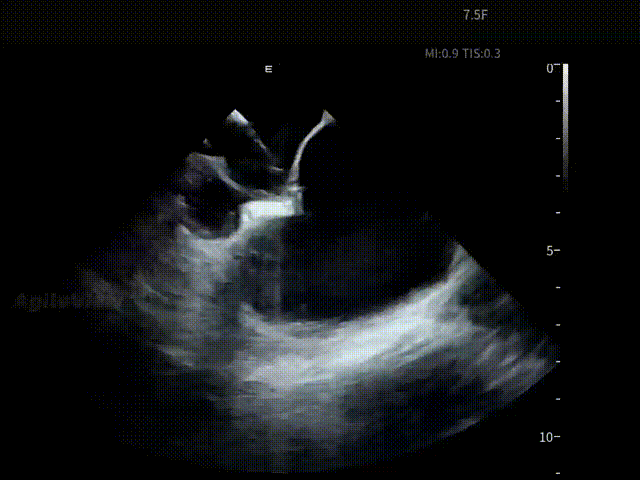

▶【术后评估:超声影像闭环,安全性确认】

手术结束前,术者操作AgileView™ ICE导管跨瓣再次对心包区域进行系统扫查,确认术后未见异常积液变化,为整台手术形成完整的安全影像闭环。

术后心包

在 ICE 实时影像的持续引导下,整台消融手术流程顺利完成。术中患者耐受良好,生命体征保持平稳,各关键操作节点均在清晰、可确认的心内超声影像基础上推进。